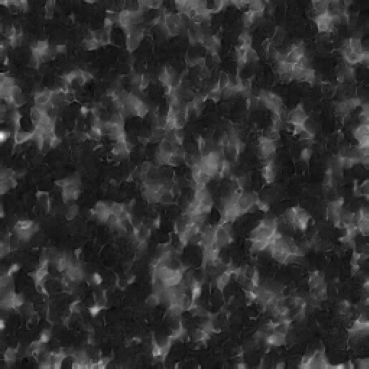

In our approach, we employ a compression factor of 4 to encode 3D medical images into the latent space. This level of compression reduces the spatial resolution of the original image (e.g., from 256×256 to 64×64 per slice), while still preserving the essential anatomical structures and semantic content. The latent representation at this scale offers a favorable trade-off between dimensionality reduction and semantic fidelity. Specifically, although fine-grained textures are simplified, key structural patterns (e.g., organ boundaries, lesion shapes) remain visually distinguishable and semantically coherent. As the compression rate increases, the latent representations become progressively more abstract. With lower compression (e.g., 2× or 4×), the latent features preserve key anatomical structures and spatial layouts, making them beneficial for our semantic image synthesis task in latent space, as the model can operate on compressed representations that retain sufficient semantic information without being overwhelmed by high-frequency noise. In contrast, higher compression rates (e.g., 8× or above) lead to a loss of fine-grained details and reduced semantic fidelity. The choice of a 4× compression thus ensures that the latent features are compact and meaningful, facilitating effective conditional generation while significantly reducing computational overhead. We therefore adopt a 4× compression as a compromise between computational efficiency and semantic preservation. The corresponding 2D slices in image space and latent space are shown in Figure 7.